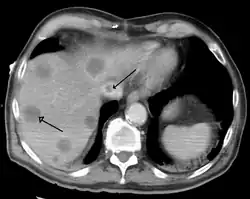

Una hepatopatía previa no diagnosticada se puede detectar tras la autopsia. Abajo se muestran imágenes de la patología:

- El cáncer hepático primario generalmente se manifiesta comohepatocarcinoma y/o colangiocarcinoma; las formas más raras incluyen angiosarcoma y hemangiosarcoma hepáticos. (Muchos cánceres hepáticos son lesiones secundarias que han metastatizado de cánceres primarios en el tracto gastrointestinal y otros órganos, como los riñones o los pulmones.)[14]